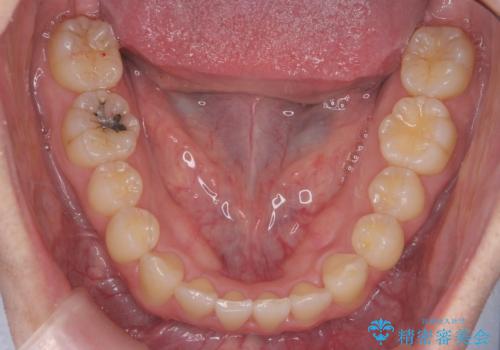

引っ込んだ前歯を並べる 歯を抜かないマウスピース矯正

- 右上の前歯が内側に入っているのを気にして来院。

右上の奥歯を後ろに移動して、前に出すスペースを確保してから並べました。

奥歯を後ろに送るために、矯正用インプラントを使用しています。